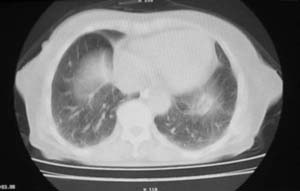

女,78岁,声嘶月余,否认有既往病史,有粉尘接触史10年。

右上肺癌伴肺内转移及纵隔淋巴转移 左上肺结核 图像有点模糊

双上肺结节融合影,周围有纤维条索影,结合粉尘接触史,首先考虑尘肺。双侧颈部有增大淋巴结,有声嘶表现,肺癌淋巴结转移不能排除。可结合颈部淋巴结活检。